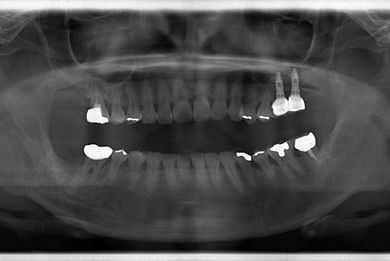

インプラントの症例写真 IMPLANT

骨再生インプラント治療+セラミック治療+歯肉歯槽骨整形

| 性別/年齢 | 女性 / 42歳 | ||||||||||||||||||||||||||||||||

| 主訴 | インプラント治療を受けたい。 | ||||||||||||||||||||||||||||||||

| 治療方針 | 左上奥欠損部分をインプラント治療にて機能的・審美的回復を行う。 | ||||||||||||||||||||||||||||||||

| 治療内容 | インプラント2本(ソケットリフト)、メタルボンドセラミック3本(メタルボンド用土台1本)、歯肉歯槽骨整形 | ||||||||||||||||||||||||||||||||

| 総治療費 | 1,227,713円 | ||||||||||||||||||||||||||||||||

| 治療期間 | 11ヶ月 |